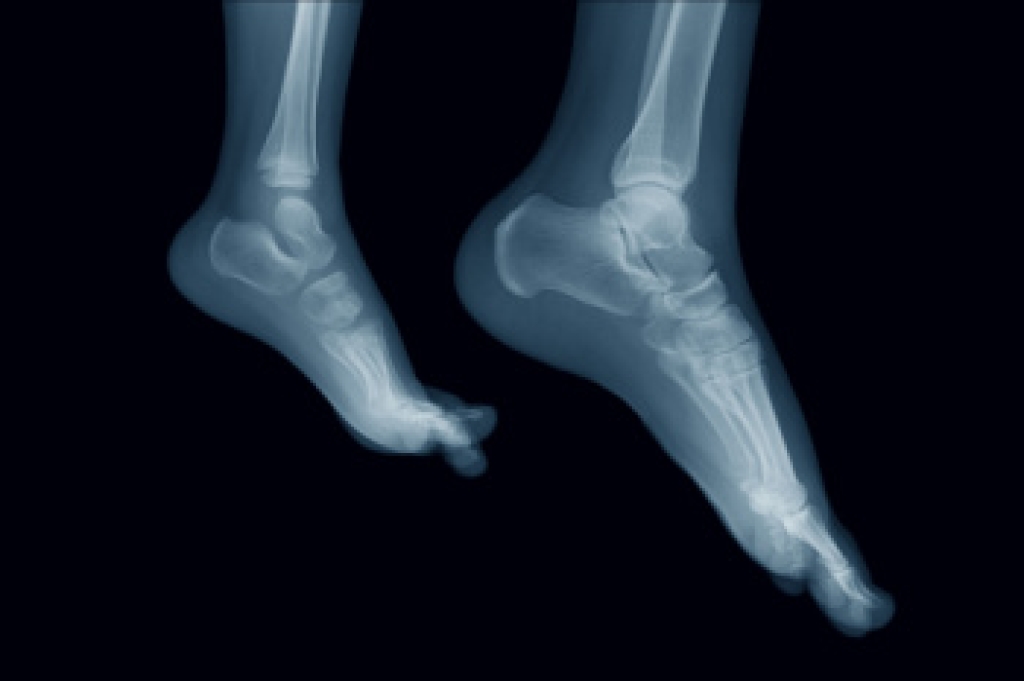

Ankle osteoarthritis develops when the joint wears down, often years after an earlier ankle injury. Damage from a past sprain or fracture can change how the ankle moves and put more pressure on the joint’s thin layer of cartilage. This can lead to swelling, stiffness, and pain that sometimes spreads into the middle or back of the foot. People may also notice grinding or popping when they point or flex their toes. In addition, the ankle can feel less flexible when walking, especially when wearing flip-flops. Extra body weight and repeated hard impact on the feet put more strain on the ankle and increase discomfort. A podiatrist can examine the ankle joint and order imaging to check the cartilage and ligaments to determine a course of treatment. Options include bracing and inserts for support or surgery when the damage is severe. If you have symptoms of osteoarthritis in the ankles, it is suggested that you make an appointment with a podiatrist for a diagnosis and treatment.